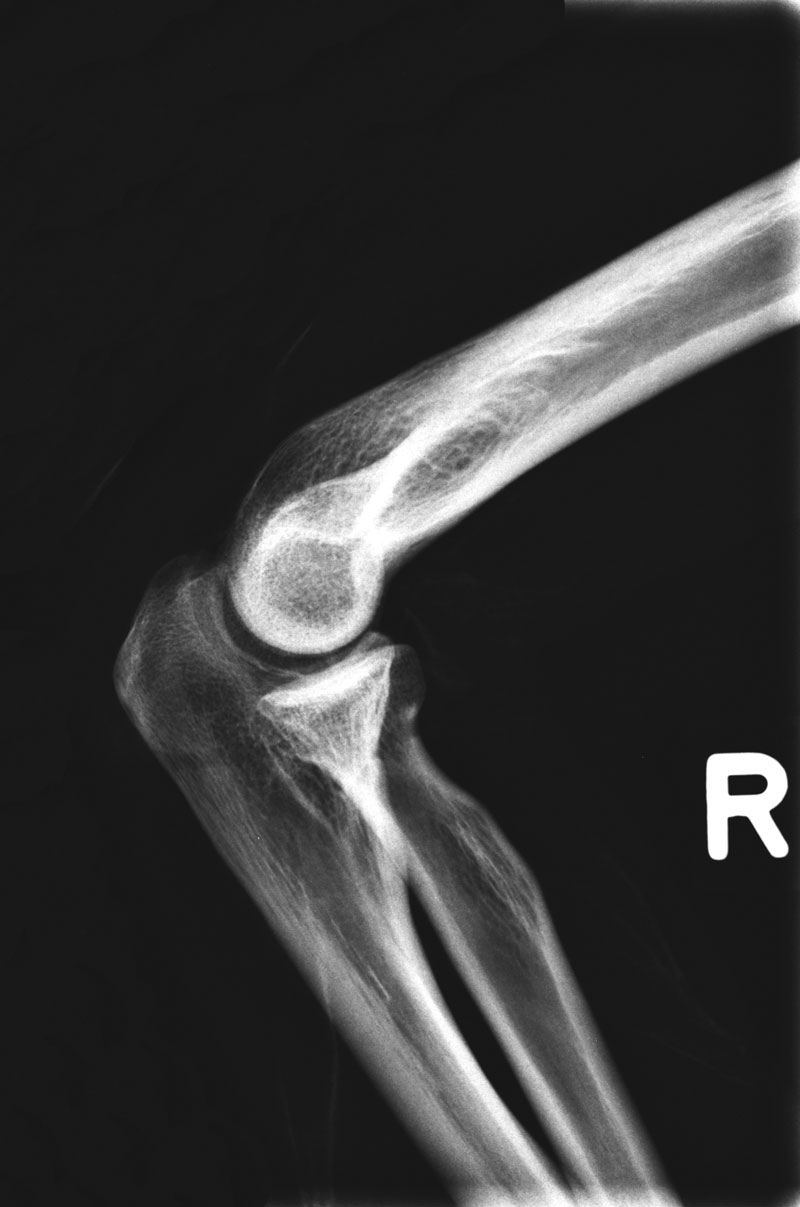

7230_7235

Röntgenphantom Fuß mit Knöchel, transparent

Unsere weltweit einmaligen Röntgenphantome enthalten echte menschliche Skelett - Teile. Dies gewährleistet erstklassige Aufnahmen und realistische Übungsbedingungen. Eine praxisnahe Röntgen - Ausbildung ist ohne diese Modelle nicht möglich. Jedes Modell wird in handwerklicher Einzelstückfertigung hergestellt und ist jeweils ein Unikat. Bedingt durch die Verwendung von echten Knochen und die individuelle Fertigung weichen die einzelnen Modelle in Größe und Beschaffenheit voneinander ab. Auch erhältlich in undurchsichtiger Ausführung (opak), Art.Nr. 7235.

7230 Röntgenphantom Fuß mit Knöchel, transparent

2.785,71 € (3315,00 €)

7235 Röntgenphantom Fuß mit Knöchel, Opak

2.756,30 € (3280,00 €)